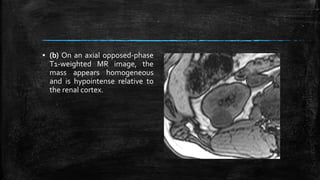

▪ (b) On an axial opposed-phase

T1-weighted MR image, the

mass appears homogeneous

and is hypointense relative to

the renal cortex.

▪ (b) Onan axial opposed-phase T1-weighted MR image, the mass appears homogeneous and is hypointense relative to the renal cortex.